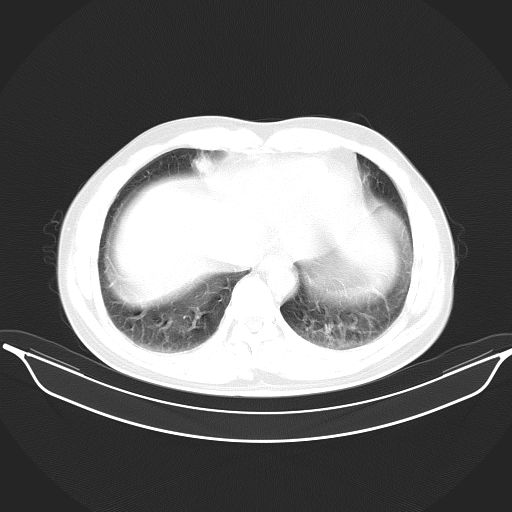

标题: CT25490:男,40岁,体检发现;无其它不适。 [打印本页]

标题: CT25490:男,40岁,体检发现;无其它不适。

考虑右下肺周围性肺癌并肺内多发转移,纵隔淋巴结转移!

支持 !考虑右下肺周围性肺癌并肺内多发转移,纵隔淋巴结转移,(气管前腔静脉后,隆突下,主动脉弓下都有了)

1、均为转移,原发灶不在肺内。2、肺癌肺转移。